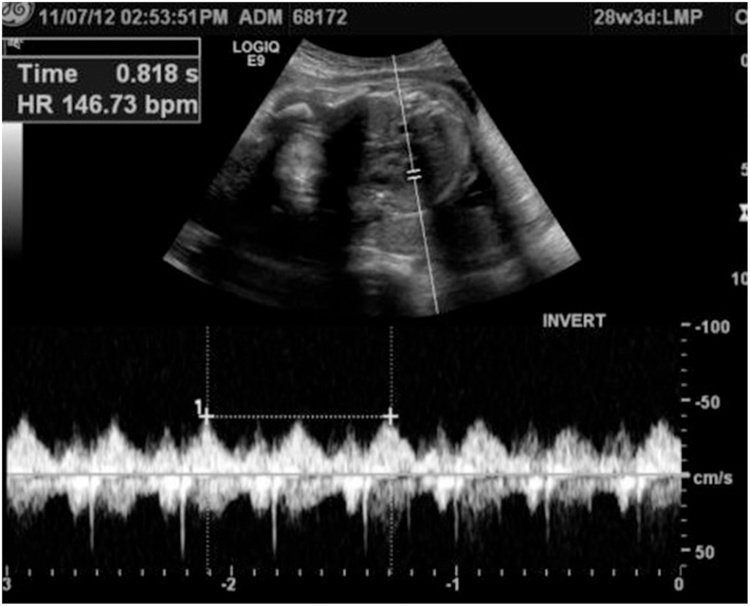

We report a case of a 22 years old pregnant female medically free, referred to us from her Obstetrician when she was complaining of abdominal pain and jaundice. Abdominal US confirmed a single intrauterine pregnancy at 28th week of gestation with appropriate growth for date and showed dilated intrahepatic ducts otherwise it was inconclusive due to the gravid uterus (Fig. 1). Her blood investigations showed a picture of cholestatic jaundice, and all other labs were within normal. So, we decided to proceed with a Magnetic resonance cholangiopancreatography (MRCP) which showed dilatation of both of the CBD (measuring 0.9 cm) & pancreatic duct, as well as an ampullary mass measuring 2 cm (Fig. 2). Later on, Endoscopic retrograde cholangiopancreatography (ERCP) with shielding of the abdomen to protect the fetus from radiation revealed an ampullary and distal CBD strictures. A punch biopsy was taken & the CBD was stented. The histopathology came as invasive adenocarcinoma & full metastatic work up was done and did not reveal any metastatic lesions. So, surgery was the best available option with the best possible outcome but we were reluctant to delay the surgery to ascertain the viability of the fetus. At 34th week of gestation induction of labor was done, both mother and the baby did well and were discharged home on 2nd day postpartum. The mother was readmitted one week later & full body CT scan repeated & there was no vascular invasion or distant metastasis.